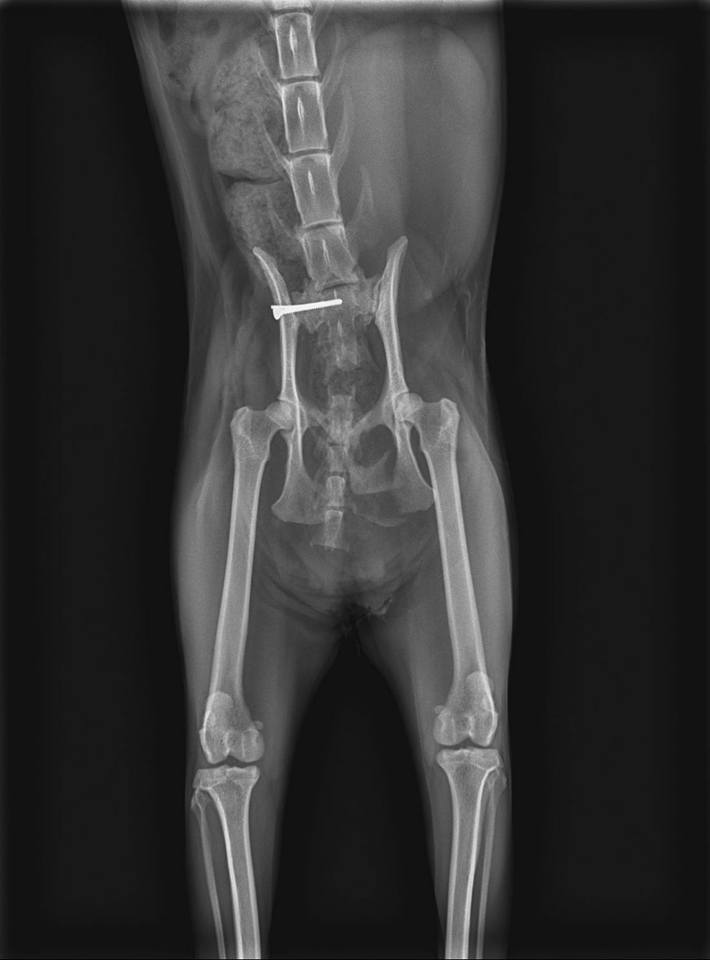

陳醫生由欣旺醫院的X光片解說:

1>貓咪脊椎斷掉的部位是脊椎尾端接尾巴前端的地方//建議將尾巴截掉對斷掉的傷口復原及貓咪往後狀態會比較好

2>貓咪右邊骨盆骨折//骨頭位置移位了//需開刀將骨頭拉回原位置固定住

因X光片無法照出神經方面的問題

陳醫生確定治療前會再補照X光片

因需要貓咪胸腔跟脊椎前段的X光片才能確認進行手術治療